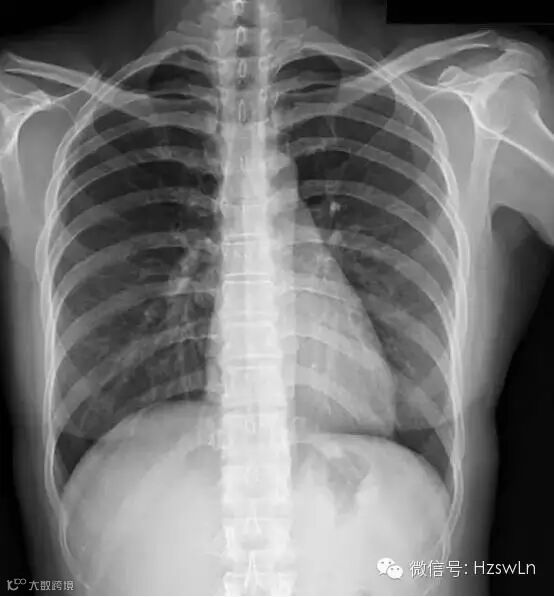

基本情况:女性,24岁轻微咳嗽3天胸片如下

•[种类和检查方法]:胸部后前位片

[描述]:

胸廓对称、无骨折和软组织肿胀;

纵膈居中,无纵膈异常增宽表现;

心影形态正常,心胸比例小于0.5;

膈肌呈穹窿样,光滑、肋膈角锐利

无异常下移或上抬表现;

双侧肺门对称、无异常肺门增大;

两肺纹理清晰,无肺内异常密度表现。

[初步诊断]

正常胸片